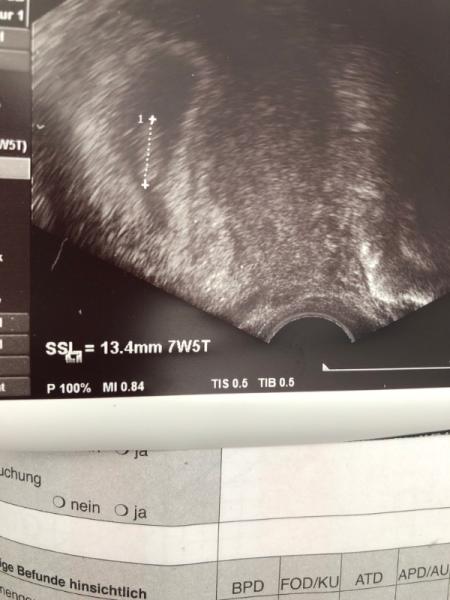

hallo, ich war da und alles ist alles so wie es sein muss herzchen hat man auch schlagen gesehen. Nur das problem ist das das bild vom ultraschal so komisch verschwommen aussieht oder wegen dem gerät so unscharf aussieht. Ich lade es mal jetzt hoch damit ihr auch was dazu sagen könnt...

Bild zu

ach schön Siehst alles ist gut. Ja jedes US Gerät ist auch anders. Ist doch sonst ein tolles Bildchen und Hauptsache alles ist gut Dann auf geht's in die nächsten Wochen Glg